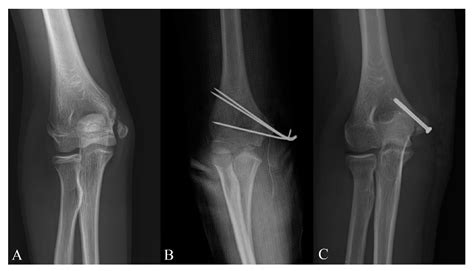

• Fractures: Fractures of the medial epicondyle can occur due to direct trauma or falls. These injuries are more common in children and adolescents, whose bones are still growing.

Diagnosis of medial epicondyle injuries often begins with a thorough physical examination, during which the healthcare provider will assess the range of motion, strength, and stability of the elbow joint. Imaging studies, such as X-rays, MRI, or ultrasound, may be used to visualize the extent of the injury and rule out other potential causes of pain.

• Open Reduction and Internal Fixation (ORIF): This procedure is used to repair fractures of the medial epicondyle, involving the use of screws, plates, or wires to stabilize the bone.